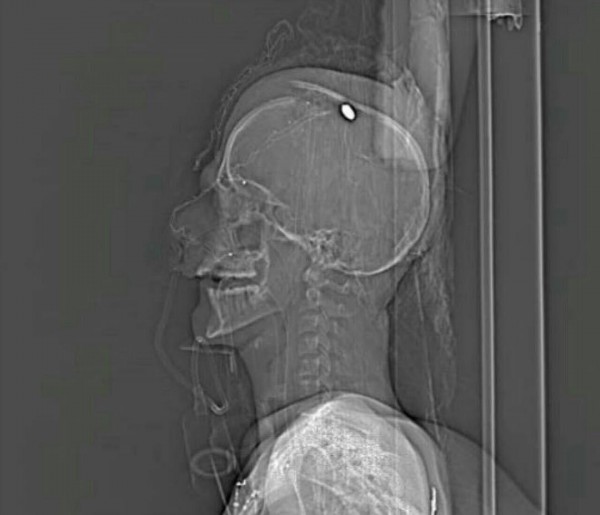

وكان الشاب مصطفى حمدان أصيب بطلقة في الرأس فجر اليوم الخميس في بلدة الدراز، أثناء هجوم قوات خاصة على المعتصمين عند منزل الزعيم الديني الأعلى آية الله الشيخ عيسى قاسم.

وأظهرت أشعة مقطعية للمصاب حمدان استقرار رصاصة في رأسه، وقال الأطباء إنه من غير الممكن إجراء جراحة لاستئصالها.